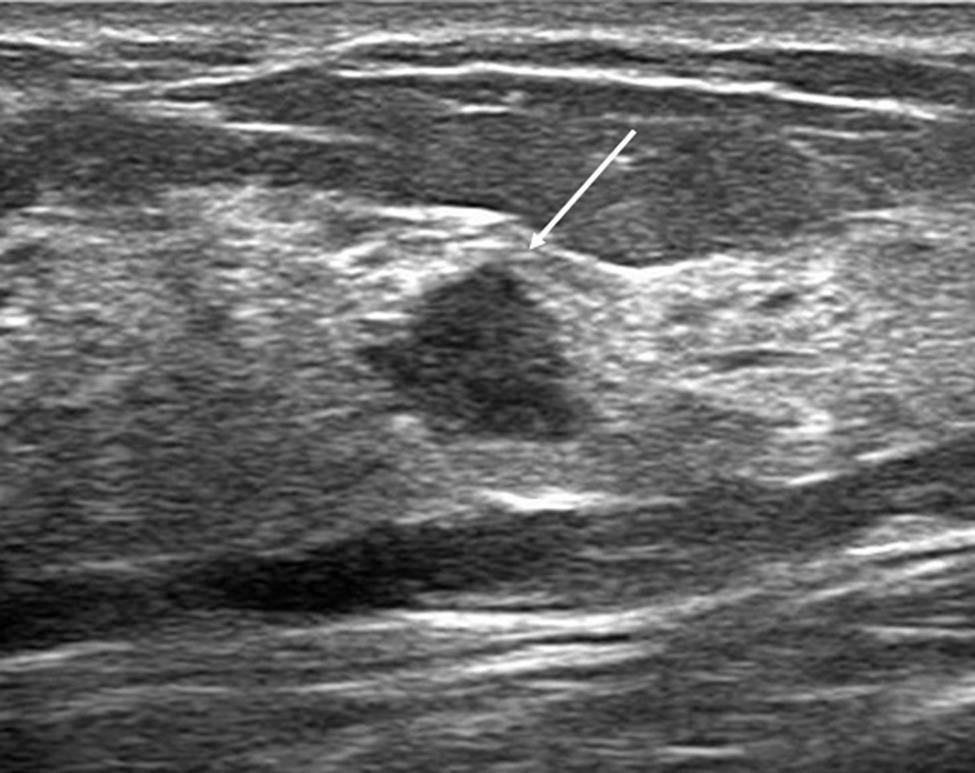

Atypical ductal hyperplasia diagnosed by US-guided core needle biopsy: clinical, pathological and US features associated with upgrading to malignancy.

To develop a predictive model to identify atypical ductal hyperplasia (ADH) that was underestimated by US-guided core needle biopsy (CNB) and to evaluate the risk factors for underestimation for ADH with intraductal papilloma diagnosed by CNB.

In this retrospective study, 300 CNB-diagnosed ADH lesions in 291 consecutive women between January 2014 and July 2023 were included and divided into training set (n = 181), internal validation set (n = 54), and external validation set (n = 65). The review included clinical, pathological, and US features, as well as final outcomes. Multivariate logistic regression was employed to establish predictive model and to evaluate risk factors. Model performance was evaluated using area under the receiver operating characteristic curve (AUC), calibration curve, decision curve analysis, and utility (patient stratification into low and high-risk groups). Model was validated both internally and externally by calculating its performance on validation sets.

The upgrade rate to malignancy was 51.0%. Predictors included in the model were age, the pathological pattern of ADH with intraductal papilloma or ADH alone, Ki-67 positivity, and imaging-pathological discordance. The AUC was 0.915 (95% CI: 0.858, 0.955) in the training set, 0.906 (95% CI: 0.785, 0.972) in the internal validation set, and 0.934 (95% CI: 0.836, 0.983) in the external validation set. Using a cutoff value of 0.11, 38.3% of nonmalignant lesions in the training set were stratified into low-risk group with an upgrade rate of 4.1%. Similar results were obtained in the validation sets. For ADH with intraductal papilloma, age and imaging-pathological discordance were the independent risk factors for malignancy upgrading.